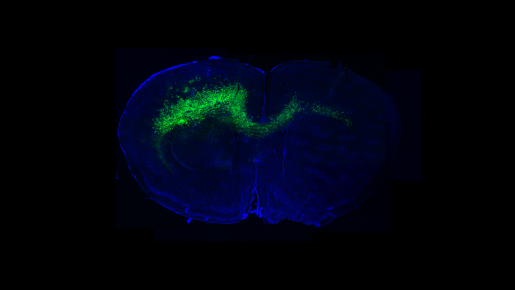

Despite rapid advances in the field of neuroscience, only a limited number of cell types in the brain are known and well characterized. In this study, researchers described an innovative approach that identified novel cellular targets and genetic pathways involved in the wiring of adult-born neurons into brain circuits. Baylor graduate student Burak Tepe was one of the primary authors of this paper.